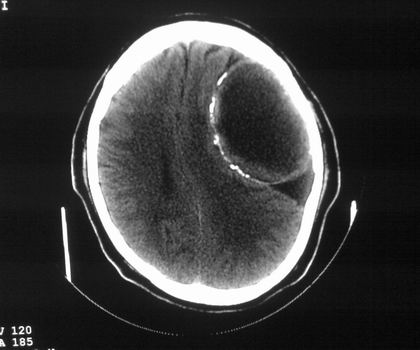

以下是引用影像孺子牛在2008-4-29 21:20:00的发言:[br]首先病变定位在脑外,根据ct密度及mri信号特征考虑慢性硬膜下血肿不连续环形钙化。

以下是引用周战梅在2008-4-29 23:12:00的发言:[br]脑外病变,蛛网膜下腔增宽,囊壁点状、环形钙化,增强扫描呈不均匀环状强化,考虑为囊性脑膜瘤可能性大,慢性脓肿、血肿机化、胆脂瘤不能除外。